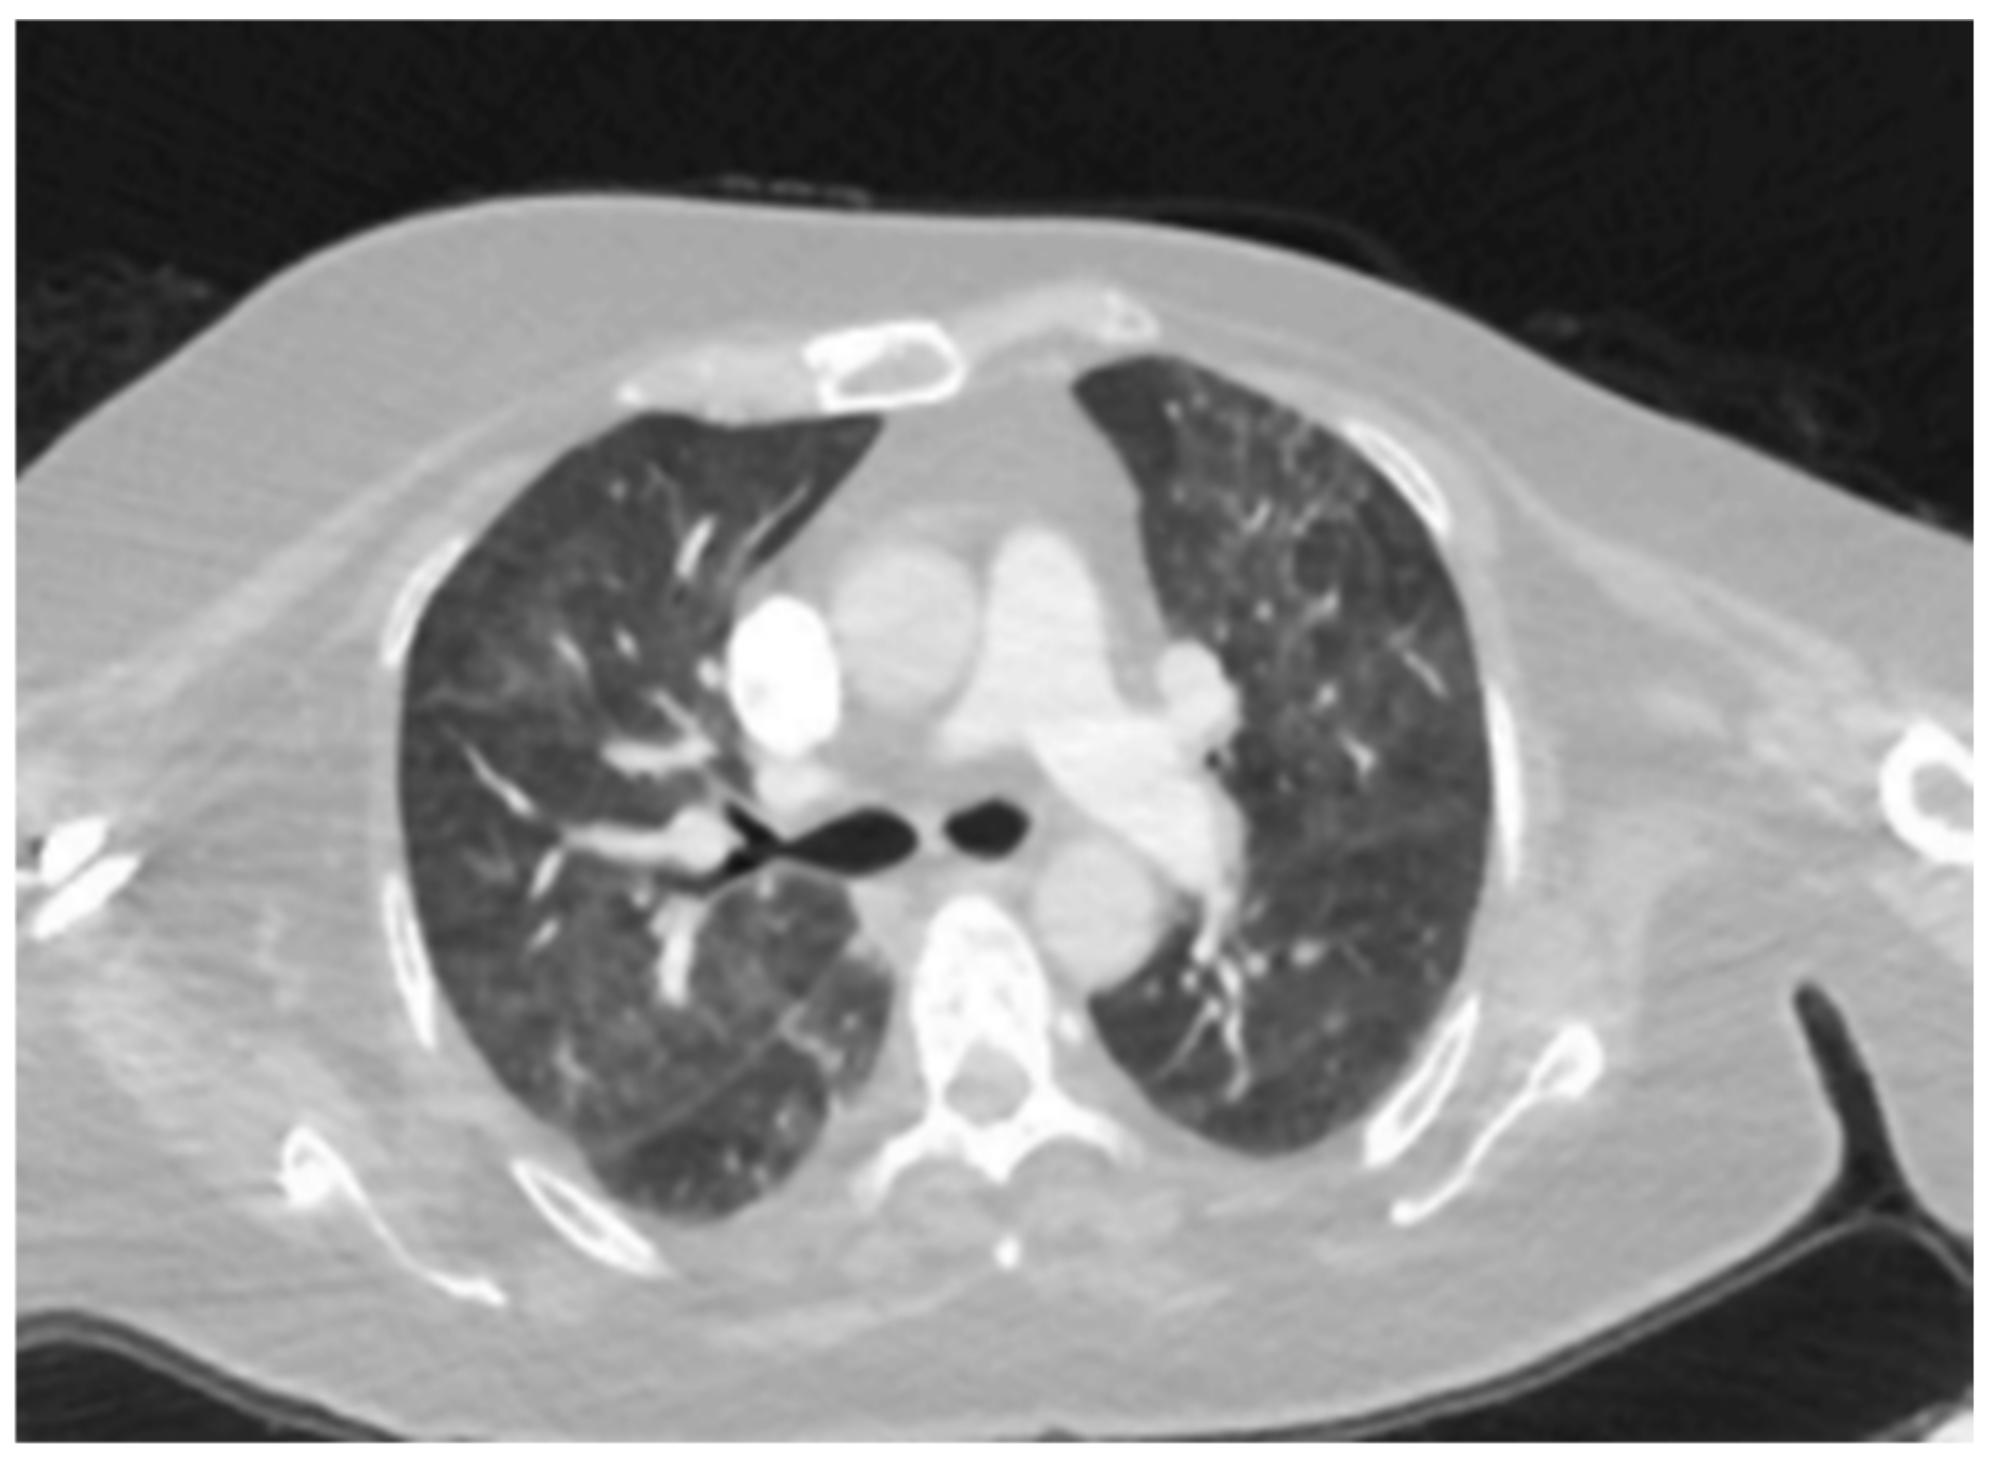

| Patient 1 | Hypersensitivity | Ribociclib | Upper lobe- |

| Pneumonitis (HP) | predominant mosaic attenuation, air | ||

| trapping, | |||

| centrilobular | |||

| nodules, and | |||

| ground-glass | |||

| opacities. (Figure 1) | |||